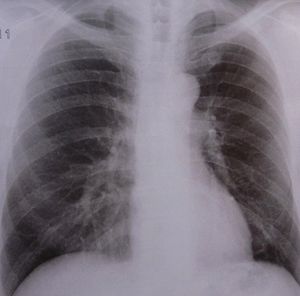

Lunge: Einige Medikamente schaden (Foto: pixelio.de, Dieter Schütz) |